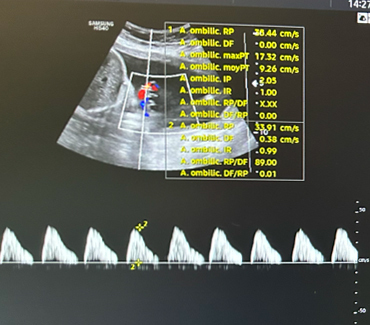

Concernant l’échographie de vitalité fœtale (figure 3), elle décrit :

– la présentation fœtale (céphalique, siège) et la position du dos ;

– la position du placenta (antérieur, postérieur, fundique, à distance ou recouvrant l’orifice interne du col) ;

– la quantité de liquide amniotique ;

– l’analyse du Doppler de l’artère ombilicale qui témoigne des échanges entre le fœtus et la mère (par ordre de gravité : diastole ombilicale positive normale ; diastole ombilicale nulle ; reverse-flow) ;

– l’analyse du Doppler de l’artère cérébrale moyenne qui peut mettre en évidence une redistribution cérébro-placentaire ou une anémie fœtale.

Figure 3 (Rodolphe Matias de Sousa, La Revue du Praticien)